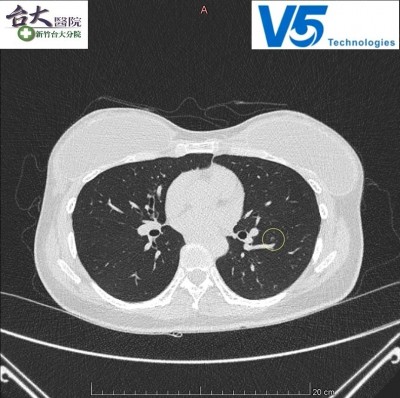

倍利科技與新竹台大分院今天(1日)簽訂「精準智慧醫療合作備忘錄」,新竹台大分院將導入倍利科技的「肺部影像輔助判讀軟體」智慧醫療平台,以AI創新科技輔助肺部小結節判讀,加快肺部結節判讀速度、減少失誤,讓早期肺癌無所遁形,雙方並將共同朝向更多影像AI研發。